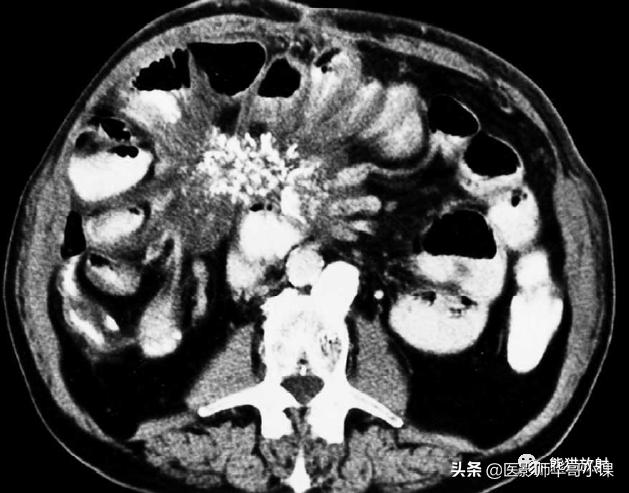

回缩性肠系膜炎CT表现 为浸润性软组织密度肿块,周围可见放射状条索影(图),这些特点可能与纤维瘤病或类癌相似。 硬化性肠系膜炎 在T1WI和T2WI图像上均呈低信号,有助于疾病的鉴别。肿块中央坏死区可见钙化(图)。该病有一定的自限性,通常预后较好。

纤维性肠系膜炎。CT表现增强CT显示大而边界模糊、广泛钙化的肠系膜软组织肿块。注意邻近的肠襻回缩及增厚。